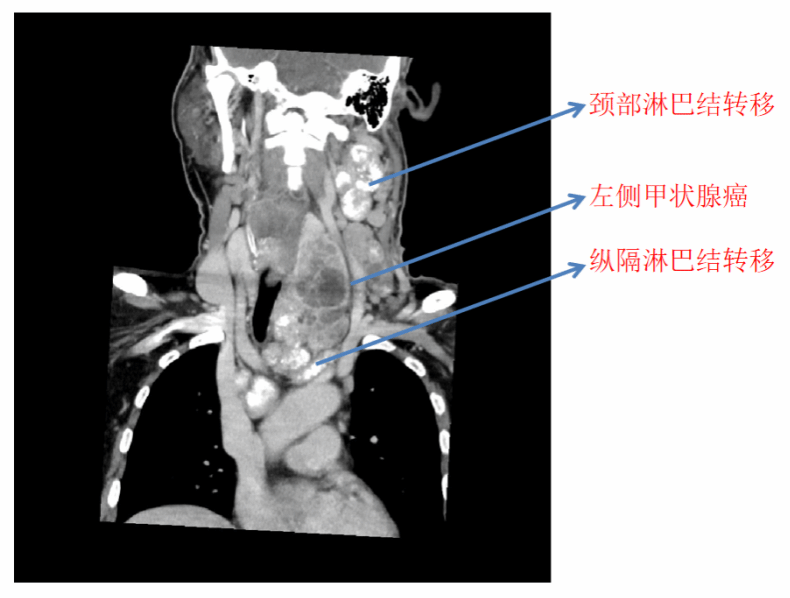

半年多前,57岁的老李在检查中发现了颈部肿物,但因肿物不痛不痒,老李便没有重视。近半年来,老李颈部的肿物越来越大,一家医院为他进行了左侧颈部肿物活检,结果显示为左侧高级别甲状腺髓样癌。PET-CT检查显示,老李颈部淋巴结广泛转移,纵隔淋巴结也未能幸免,疾病的恶性程度极高。老李先后去到多家医院,却都被告知没有好的解决办法,最后辗转来到北医三院。

患者颈部、纵隔淋巴结广泛转移